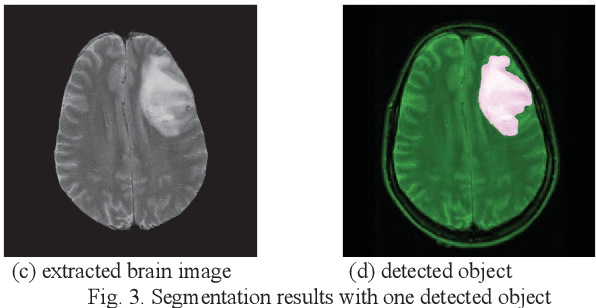

BG

FG

Segmentation